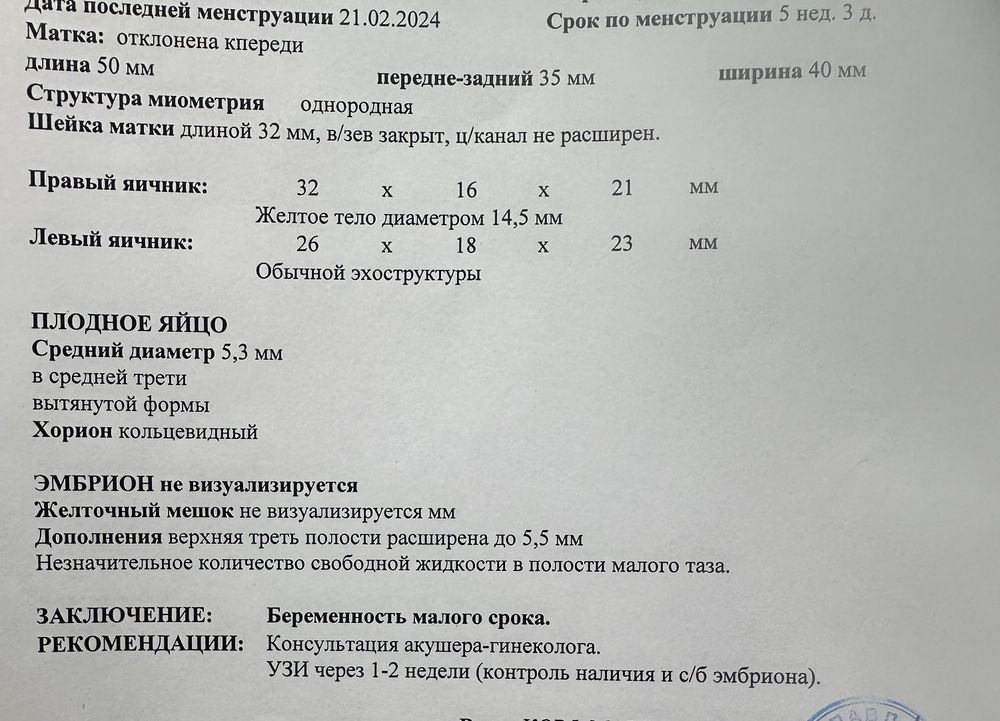

Девочки, всем привет❤️ Вчера получила хгч 2000, поэтому сегодня помчала на узи. У меня была поздняя овуляция ( определяла по тестам ), сегодня получается 18-19 ДПО. На узи не нашли эмбрион, но доктор сказала, что это в связи с поздней овуляцией.

При таком хгч и размере пя ни о каком эмбрионе и речи быть не может,еще даже жм нет,странный врач.